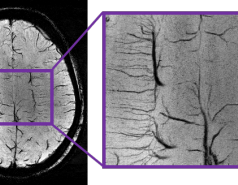

High resolution anatomical imaging